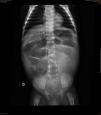

Descrição do casoPaciente masculino, negro, encaminhado ao hospital terciário aos dois meses de vida com diagnóstico de diarreia intratável e vômitos havia 22 dias. Evoluiu com choque hipovolêmico e acidose metabólica refratária. Trazia radiografia simples de abdome que mostrava distensão generalizada de alças intestinais (fig. 1) e tomografia computadorizada que indicava ausência de progressão do contraste enteral para segmentos colônicos distais.